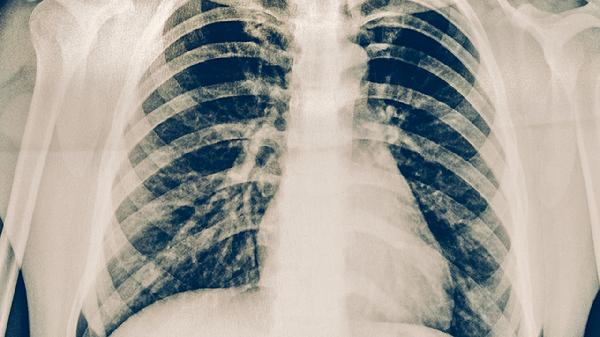

肺结核患者可遵医嘱使用异烟肼片、利福平胶囊、吡嗪酰胺片、乙胺丁醇片、链霉素注射液等抗结核药物。肺结核是由结核分枝杆菌感染引起的慢性传染病,需规范联合用药以减少耐药性,具体用药方案需由医生根据病情制定。

肺结核患者除规范用药外,需保持充足营养摄入,每日保证优质蛋白如鸡蛋、鱼肉及新鲜蔬菜水果。注意居室通风消毒,咳嗽喷嚏时掩住口鼻,痰液需焚烧处理。治疗期间避免劳累,保证8小时睡眠,戒烟限酒。严格遵医嘱完成6-8个月全程治疗,即使症状消失也不可自行停药,定期复查胸部影像学和痰菌检测。出现药物不良反应应及时就医调整方案,耐药结核患者需进行药物敏感性试验指导用药。